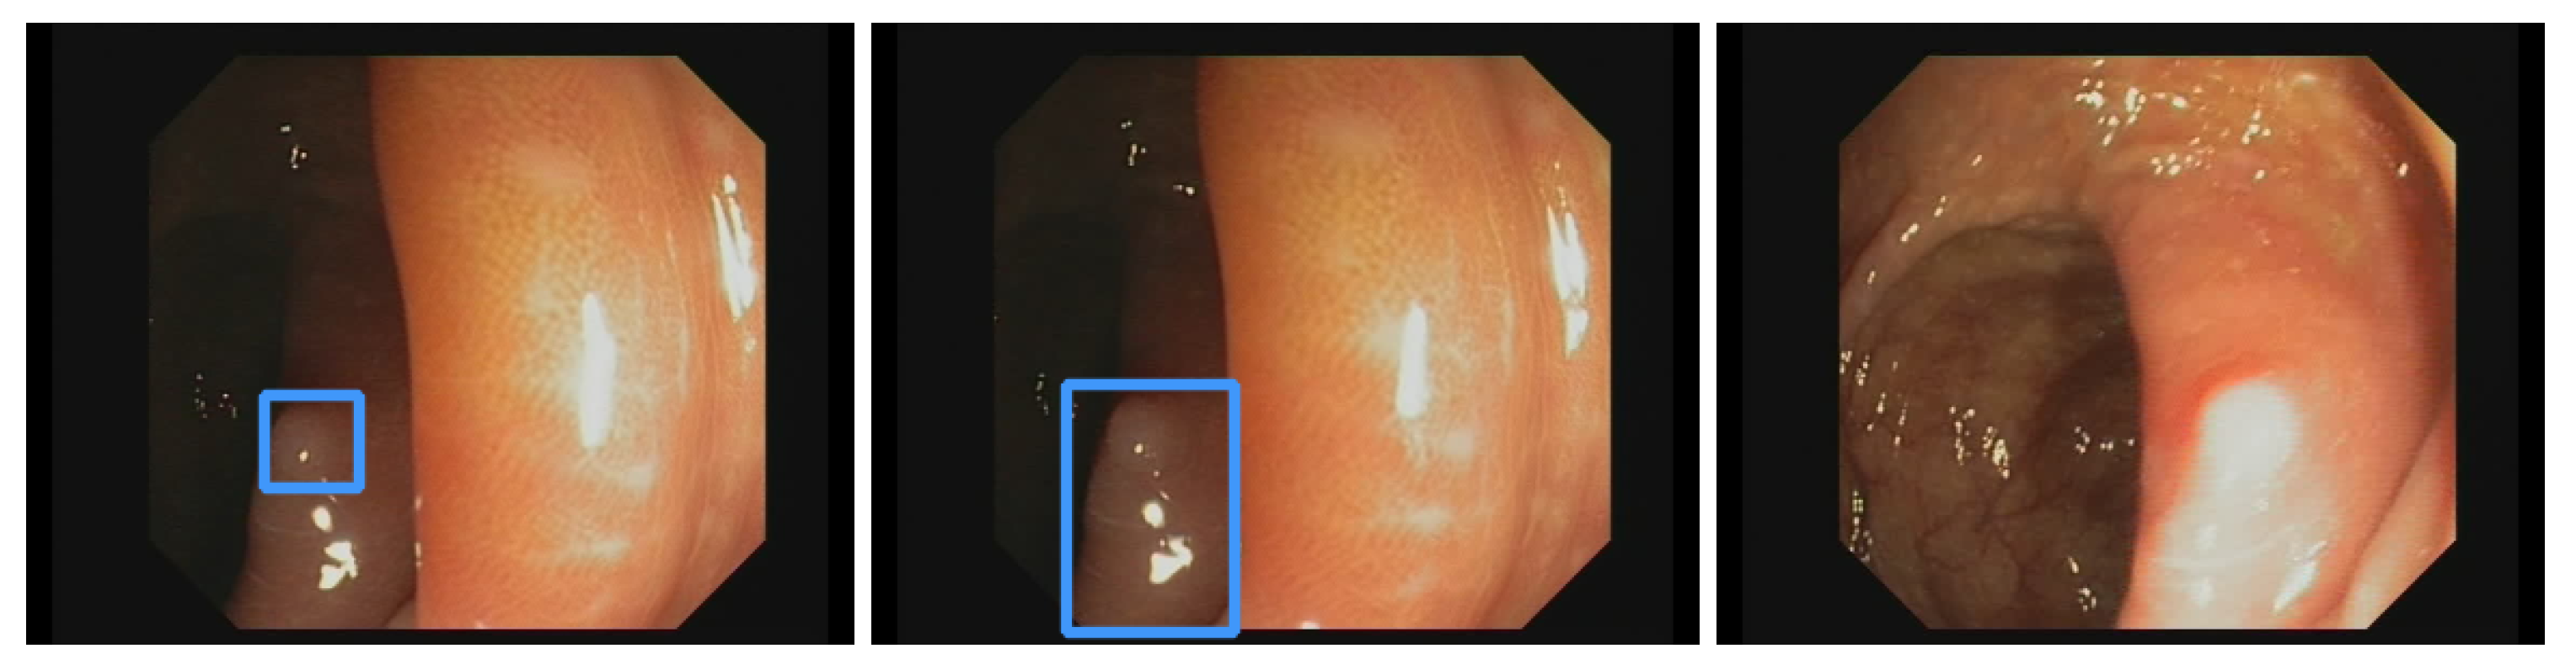

Our own validation set (EndoData) allows us to detect polyps more precisely and accurately. Table 8 shows an overview of the videos in the dataset and Figure 13 shows examples of the dataset. The EndoData dataset records sequences as the polyp appears in the scene. Therefore, polyps are marked precisely with their first appearance. In comparison, the polyp sequence of the CVC-VideoClinicDB dataset might not start when the polyp is already detected. Those early seconds are crucial as the gastroenterologist has to identify and not miss the polyp during this time. If the polyp is not detected in the early sequence, it increases the risk of missing it. As we like to focus on this early detection, we introduce a second metric that can just be evaluated with a dataset like ours. This metric marks the seconds from first seeing the polyp to first detecting the polyp. We call it first detection time (FDT). Additionally, we compute the FPs and the false positive rate (FPR) per video (Table 10 and Table 11).

Figure 13.

Example images of the Endodata dataset for evaluation.

The evaluation for FDT is shown in Table 10. For the YOLOv5 (base), only video 4 does not receive a delay in detection. Nevertheless, all polyps are detected at least once with every algorithm. The FDT of YOLOv5 (base) is inferior in all videos to the other models. The Faster R-CNN algorithm does recognize the polyp in the first frame in videos 1, 3, 4, and 10 for YOLOv5 (adv.), REPP, and RT-REPP. The FDT for these three models does not differ except for video 7. This difference is due to REPP and RT-REPP removing the detection in the post-processing process. Those three approaches also detect the polyps in the first frame for videos 1, 3, 4, and 10, like Faster R-CNN. For 9 out of the 10 videos, FDT is under 1 s; therefore, the polyp should be sufficiently detected to show the gastroenterologist its position. Nevertheless, in video 7 there is a FDT of 2.6 s. Such a late detection of a polyp may miss the polyp for the gastroenterologist. However, REPP and RT-REPP are reducing the number of FPs from an average of 113.5 to 78.3 and 91.3.